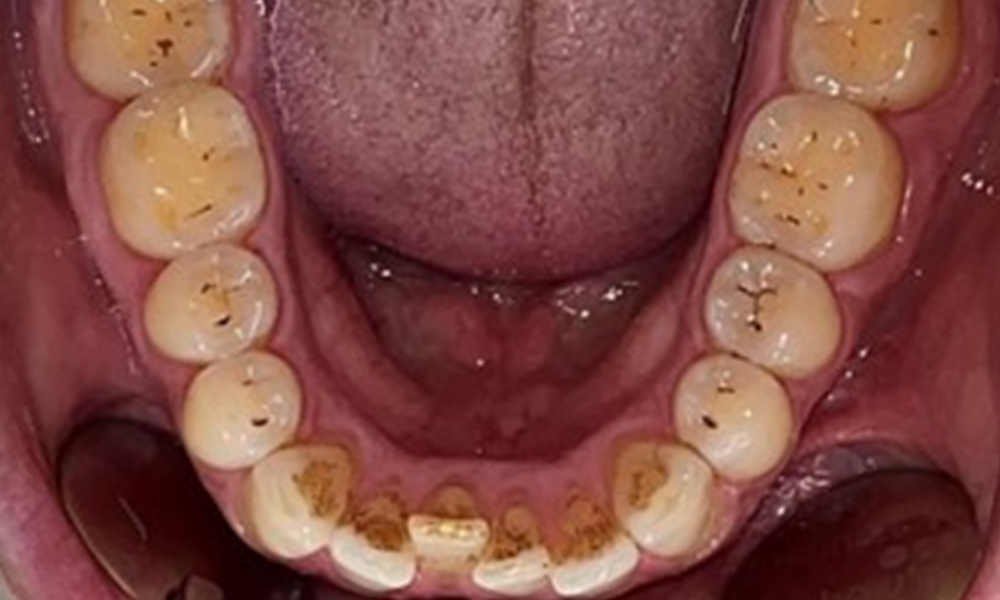

Dental findings

The patient has full dentition with a total of 28 teeth. There were noteworthy erosions and attritions. (Fig. 4, Fig. 5). Due to bruxism, the patient has been wearing a splint with an adjusted bite block at night for many years. The erosions were caused by long-term consumption of isotonic beverages. No periodontal bone loss or active caries were observed.